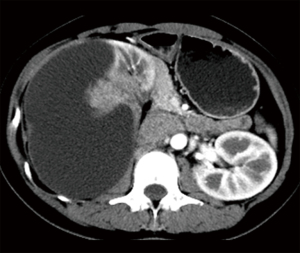

A 34-year-old Chinese woman complaining of an increasingly right-sided lumbago after she discovered a palpable right lumbar mass since November 2012. After admission, computed tomography (CT) imaging showed a 12.2 cm × 7.9 cm × 13.2 cm mass in her right kidney with enlarged retroperitoneal lymph nodes (RPLNs) in close proximity to major renal and abdominal blood vessels, without any distant metastasis (Figure 1) and multiple uterine fibroids were identified on PET-CT. On December 7, 2012, she underwent radical right-sided nephrectomy with RPLNs dissection and was pathologically diagnosed as pT2N1M0 nccRCC with the morphological feature of type 2 papillary renal cell carcinoma without adjuvant therapy. The timeline of this case is shown in Figure 2.